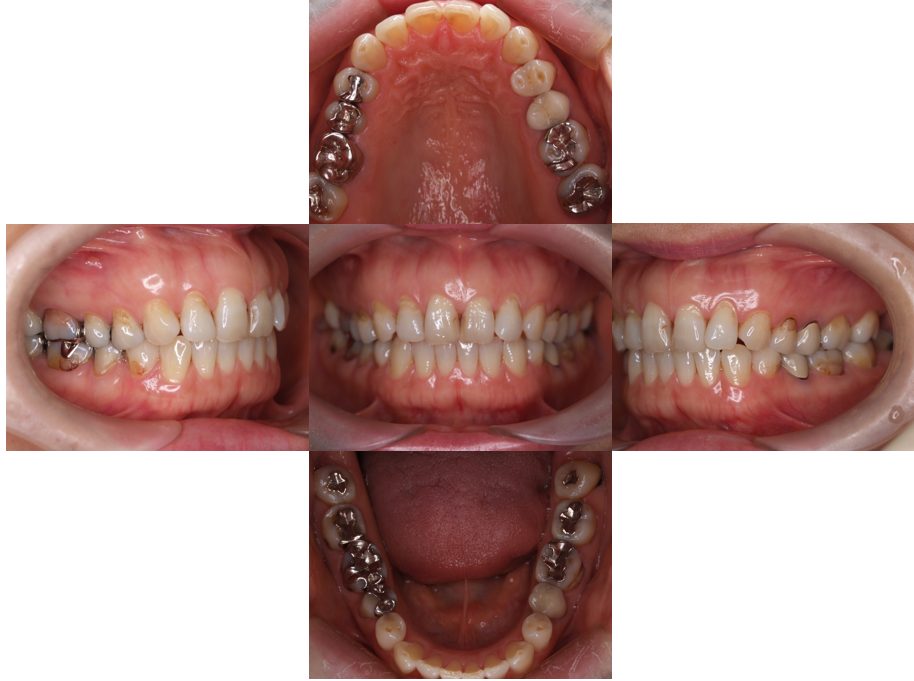

| 主訴 | 過去作成した右下の被せ物がずれて入っており、たまに腫れる。歯並びも気になる。 |

| 治療内容 | 矯正治療を行いました。 |

| 治療費 | 800,000円(税込み) |

| 治療期間 | 2年半(矯正治療期間 2年) |

| 治療回数 | 30回 |

| 想定されたリスク | 術前に基礎資料を整え分析し、セットアップモデル等でシミュレーションをしておかないと、予定通りの治療が行えないリスクがあった。 |